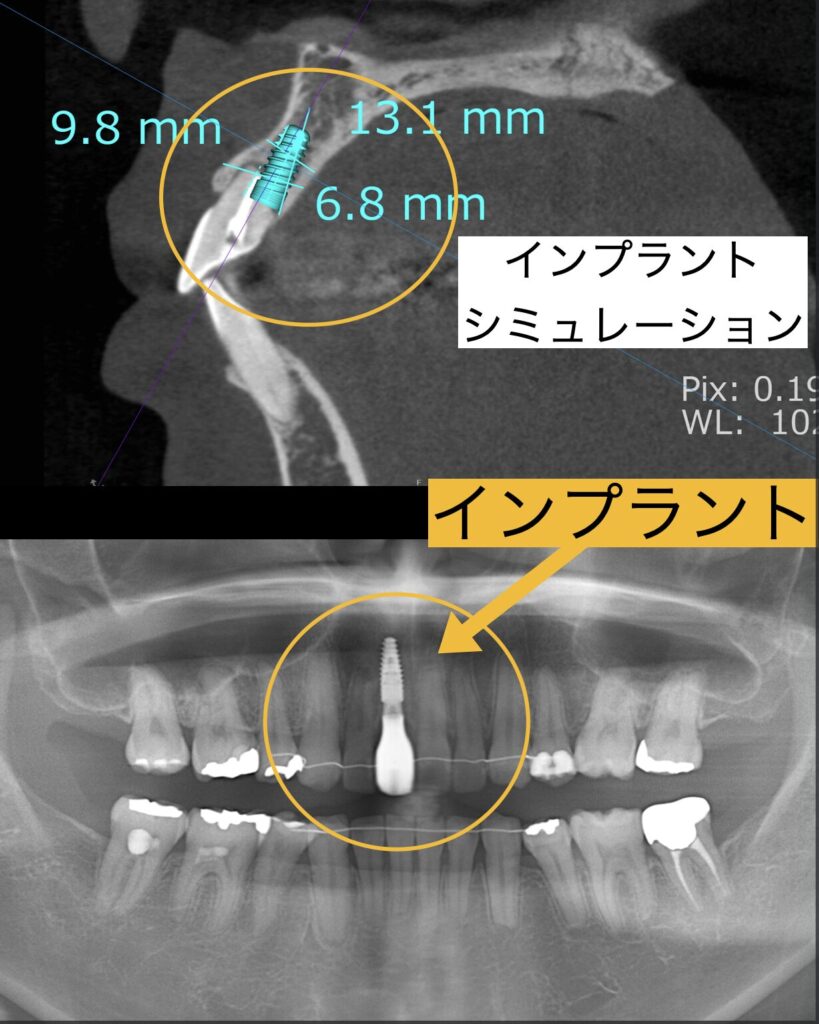

私たちはまず、理想的な噛み合わせをデジタルで設計し、ゴールを明確に設定しました。そして、そのシミュレーションに基づいて精密にインプラントを埋入。すべての治療が完了するまで、1年もかかりませんでした。

骨がないと他院で言われて諦めていた患者様の体験談

骨がないからインプラントができないと言われている患者様が大勢いらっしゃいます。実はほとんどの場合、そんなことはありません。そう言われた方も決してあきらめないでください。

骨は無ければ造ることが可能です。そして、最近では骨が無くてもインプラント治療が可能な機器やシステムができてきました。

この患者様は1ミリほどしか骨が無くインプラントが難しいと言われていた患者様ですが、骨を12ミリほど造ることができ、問題なくインプラントを埋入することができました。骨が無くてもインプラントはできますので、別の医院でセカンドオピニオンを受けられることをおすすめします。